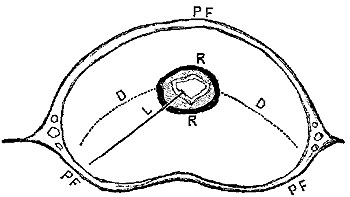

The superficial femoral is the name given to the main trunk between the origin of the profunda, and the point at which, passing through the tendon of the adductor magnus, it receives the name of popliteal. During this long course it gives off no branch large enough or regular enough to receive a name, except one, the anastomotica magna, which rises in Hunter's canal, close to the end of the vessel, so in that respect it is peculiarly suitable for the application of a ligature. Again, in the upper part of its course, it is superficial, being covered only by skin and fascia. A short notice of its most important anatomical relations is necessary.

For the first two inches or two inches and a half of its separate existence, the superficial femoral lies in Scarpa's triangle, covered, as we said, only by skin and fascia. This triangle is formed by the sartorius and adductor longus muscles which meet at its apex, and by Poupart's ligament, which defines its base. The artery lies almost exactly in the centre of the space, and at the apex is covered by the sartorius muscle. The spot where it goes under the sartorius is the one selected for the application of the ligature. The femoral vein lies to the inner side of the femoral artery in this triangle, but their mutual relations vary with the portion of the limb; for, on the level of Poupart's ligament, the artery and vein lie side by side on the same plane, but in different compartments of their sheath; as the artery dives below the sartorius, the vein is still on the inside, but on a plane slightly posterior; while, by the time they reach Hunter's canal, the vein has got completely behind the artery. The separate compartments of the sheath in which the vessels lie are much less marked as the vessels go down the limb, the septum between the artery and the vein being in most cases very ill marked, even{18} at the level where the ligature is applied. The anterior crural nerve, which on the level of Poupart's ligament lay outside of the artery and on a plane somewhat posterior, has divided into numerous branches before it reaches the point of ligature. One of its branches requires to be mentioned, and may sometimes be noticed and avoided during the operation, namely the internal saphenous nerve, which, first lying external to the artery, crosses it in front, reaching its inner side just before it enters Hunter's canal, where it leaves the vessel accompanying the anastomotica magna branch.

Operation of Ligature of the Femoral—Scarpa's Space.—The patient being placed on his back, and being brought very thoroughly under chloroform, the knee of the affected limb should be bent at an angle of about 120°, and supported on a pillow. Having previously ascertained the angle of junction of the sartorius and adductor, the surgeon should make an incision (Plate I. fig. 5) just over the pulsations of the vessel, in the middle line of the space, having its lower end quite over the sartorius muscle, and its upper one, at a distance from two and a half to three and a half inches, varying according to the amount of fat and muscle. The saphena vein can generally be recognised, and is almost always safe out of the way of this incision at its inner side.

The first incision should divide the skin, superficial fascia, and fat, quite down to the fascia lata. The edges of the wound being held apart, the fascia should be carefully divided, and the sartorius exposed; its fibres can generally be easily enough recognised by their oblique direction; once recognised, the fascia should be dissected from it till its inner edge be gained, the corner of which should then be turned so that it may be held outwards by an assistant with a blunt hook. The sheath of the vessels is now exposed, and after having thoroughly{19} satisfied himself of the position of the artery by the pulsation, the surgeon should carefully raise a portion of the sheath with the dissecting forceps, and open it freely enough to allow the coats of the artery to be distinctly seen. If the parts are deep, as in a fat or muscular patient, great advantage will be gained by seizing one edge of the sheath by a pair of spring forceps, and committing it to the care of an assistant, while the operator holds the other in his dissecting forceps; there is thus no fear of losing the orifice of the sheath, which without this precaution may easily happen, from the parts being confused with blood, or the position altered by movements of the patient. Now comes the stage of the operation on which, more than on anything else, success or failure depends. A small portion of the vessel must be cleaned for the reception of the ligature, and it must be thoroughly cleaned, so that the needle may be passed round it without bruising of the coats, or rupture of an unnecessary number of the vasa vasorum by rough attempts to force a passage for it. Hence all compromises, such as blunted instruments, silver knives, and the like, are dangerous, for in trying to avoid the Scylla of wounding the artery, they fall into the Charybdis, on the one hand, of isolating too much of the vessel and causing gangrene from want of vascular supply, or, on the other, expose the vein to the danger of injury by the aneurism-needle in their attempts to force it round an uncleaned vessel.

The needle should in most cases be passed from the inner side, care being taken to avoid including the vein which is on the inner side and behind the vessel; the internal saphenous nerve, if seen, should be avoided. The needle must not be passed quite round the vessel raising it up, still less must the vessel be held up on the needle, as used to be done, as if the surgeon was surprised at his own success, but the needle should be passed just far enough to expose the end of the ligature,{20} which must be seized by forceps and cautiously drawn through. It must then be tied very firmly and secured with a reef knot.

The edges of the wound must be brought into accurate apposition, and secured by one or two stitches. If antiseptics are used, drainage should be provided for.

From the very fact that ligature of the superficial femoral is a remarkably successful operation in causing consolidation of the aneurism and a rapid cure, there is also a corresponding danger that the limb be not sufficiently supplied with blood at first. The limb may very possibly become cold, and remain so for some hours at least after the operation. To avoid this as far as possible, it should be wrapped in cotton wadding, and very great care should be taken that it be not over-stimulated by hot applications, friction, or the like, any of which measures might very likely excite reaction, which would result in gangrene.

Complete rest of the limb and of the whole body must be enjoined; the food must be nourishing and in moderate quantity. The chief danger is from gangrene of the limb, which is especially apt to result when the vein is wounded, or even too much handled during the operation.

When properly performed, and in suitable cases, the operation is very successful. Mr. Syme tied this artery for aneurism thirty-seven times, and of these every one recovered. The statistics of Norris and Porta, who collected all the cases in which ligature of the femoral had been employed for any cause, show a mortality of somewhat less than one in four. Rabe's table up to 1869 with the additional cases collected by Mr. Barwell to 1880 gives 297 cases with 53 deaths.[9] Mr. Hutchinson's table, again, of fifty cases collected from the records of Metropolitan Hospitals, shows the very{21} startling result of sixteen deaths out of the fifty cases, or a mortality, in round numbers, of one-third.